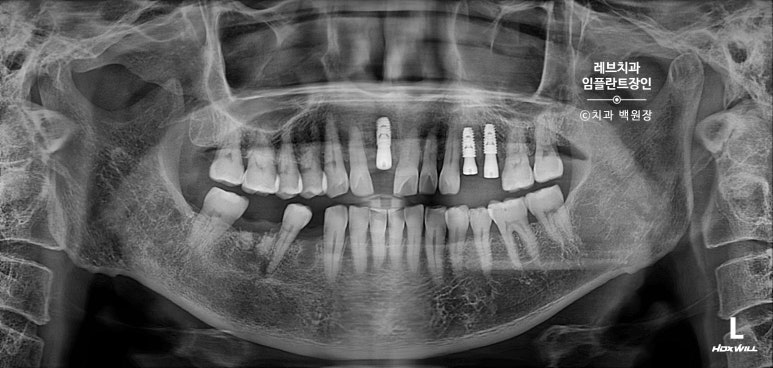

한 달 뒤 임플란트 2개를 심어드렸습니다.

광범위한 뼈이식도 함께!

완성 후 촬영한 치과용 방사선 엑스레이 사진에서도, 깔끔하게 완성된 보철물을 보실 수 있을겁니다.